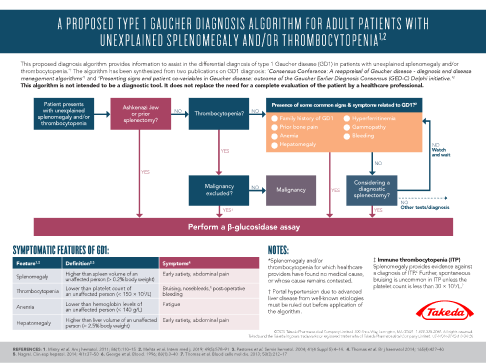

This algorithm* provides information to assist in the differential diagnosis of GD1 in patients with unexplained splenomegaly and/or thrombocytopenia.

This algorithm is not intended to be a diagnostic tool. It does not replace the need for a complete evaluation of the patient by a healthcare professional.

In cases of splenomegaly and/or thrombocytopenia it is important to include GD1 in differential diagnoses in order to avoid potentially harmful splenectomy or irreversible complications.7,15

*This algorithm has been synthesized from two publications on type 1 Gaucher disease diagnosis: ‘Consensus Conference: A reappraisal of Gaucher disease – diagnosis and disease management algorithms’ and ‘Presenting signs and patient covariables in Gaucher disease: outcome of the Gaucher Earlier Diagnosis Consensus (GED-C) Delphi initiative.’3,13